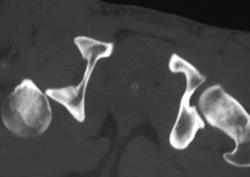

Non Union 1st Rib Fractures